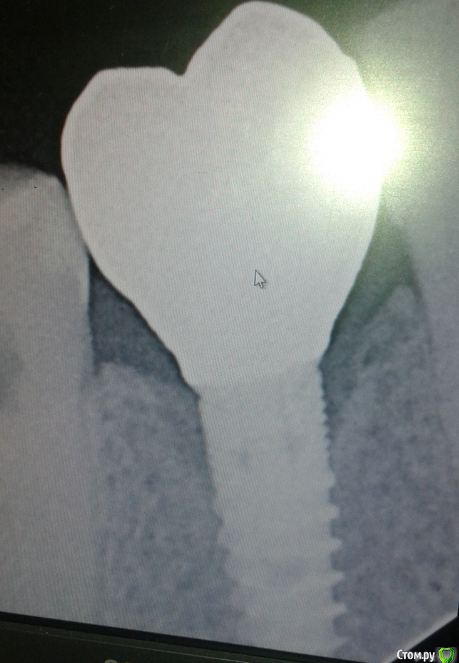

g_kot Опубликовано 26 мая, 2015 Автор Поделиться Опубликовано 26 мая, 2015 (изменено) вот только что есть с щечной стороны был костный дефект поэтому имплант смещен небно и стоит под углом (что видно по шахте абатмента на прошлом фото) Изменено 26 мая, 2015 пользователем g_kot Ссылка на комментарий

faity Опубликовано 26 мая, 2015 Поделиться Опубликовано 26 мая, 2015 не думаю что будут проблемы, угол не очень критичный, на индивидуальных аббатментах вообще красиво получится 2 Ссылка на комментарий

g_kot Опубликовано 26 мая, 2015 Автор Поделиться Опубликовано 26 мая, 2015 (изменено) faity, есть смысл ставить угловой абатмент? так как на стандартном (прямом) шахта ушла аж в самый край коронки и как доказать это своему доктору... Изменено 26 мая, 2015 пользователем g_kot Ссылка на комментарий

faity Опубликовано 26 мая, 2015 Поделиться Опубликовано 26 мая, 2015 по сути импланту и окружающей его кости всё равно куда распределять нагрузку, главное чтобы поставлен был правильно и кости вокруг было достаточно. индивидуальный аббатмент может исправить даже угол кривизны рук оператора, делайте его, не стесняйтесь 2 Ссылка на комментарий

g_kot Опубликовано 17 октября, 2015 Автор Поделиться Опубликовано 17 октября, 2015 Добрый день всем. Сегодня закончили протезирование. В принципе я доволен конечным результатом, но снимок спустя чуть больше года после установки не порадовал резорбцией. Что скажите? Жить будет? Ссылка на комментарий